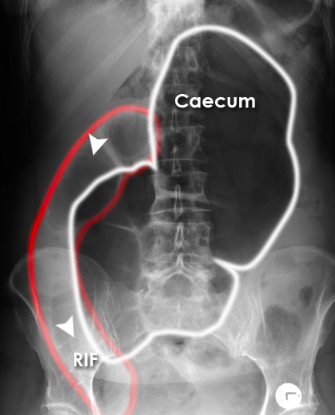

Patient with abdominal pain, vomiting, and constipation. What is the radiological diagnosis?

Caecal volvulus

Sigmoid volvulus

Small bowel obstruction

Perforation

Normal

A